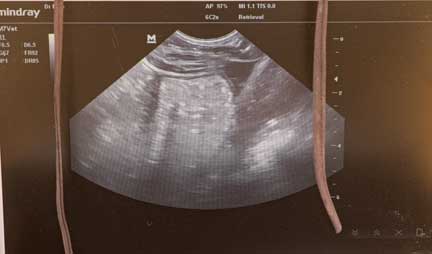

Vet team looking at ultrasound to determine if pregnant

Checking this female with ultrasound for pregnancy

Ultrasound screen of Ultrasound of pregnant rhino

Affirmative on that pregnancy!